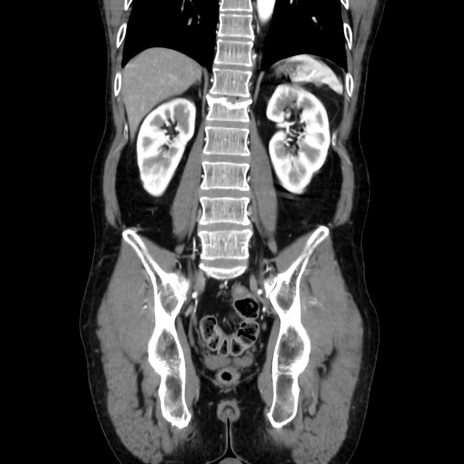

症例37(冠状断像)

【症例】40歳代 男性

【主訴】腹痛

【現病歴】4時間ほど前に電車に乗車中に臍部上より腹痛出現。徐々に増悪し起立困難となり、救急外来受診。生ものは数日食べていない。今朝お雑煮を食べた。

【身体所見】BT 36.8℃、BP 117/84mmHg、HR 91/min、SpO2 97%、苦悶様、腹部:臍上部広範囲圧痛あり、反跳痛±

【データ】WBC 8100、CRP 0.03